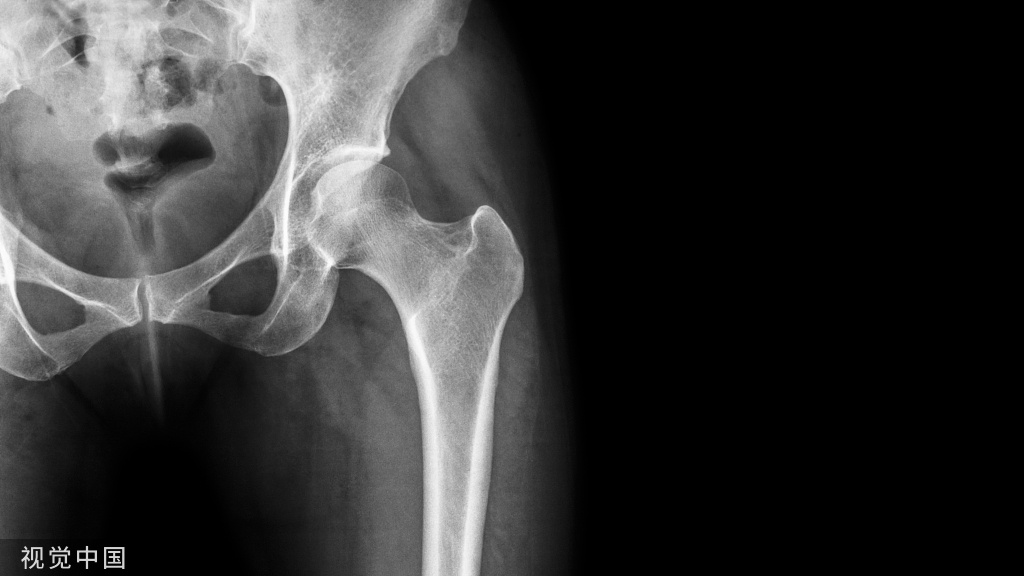

智齿在X线片上很清晰▼